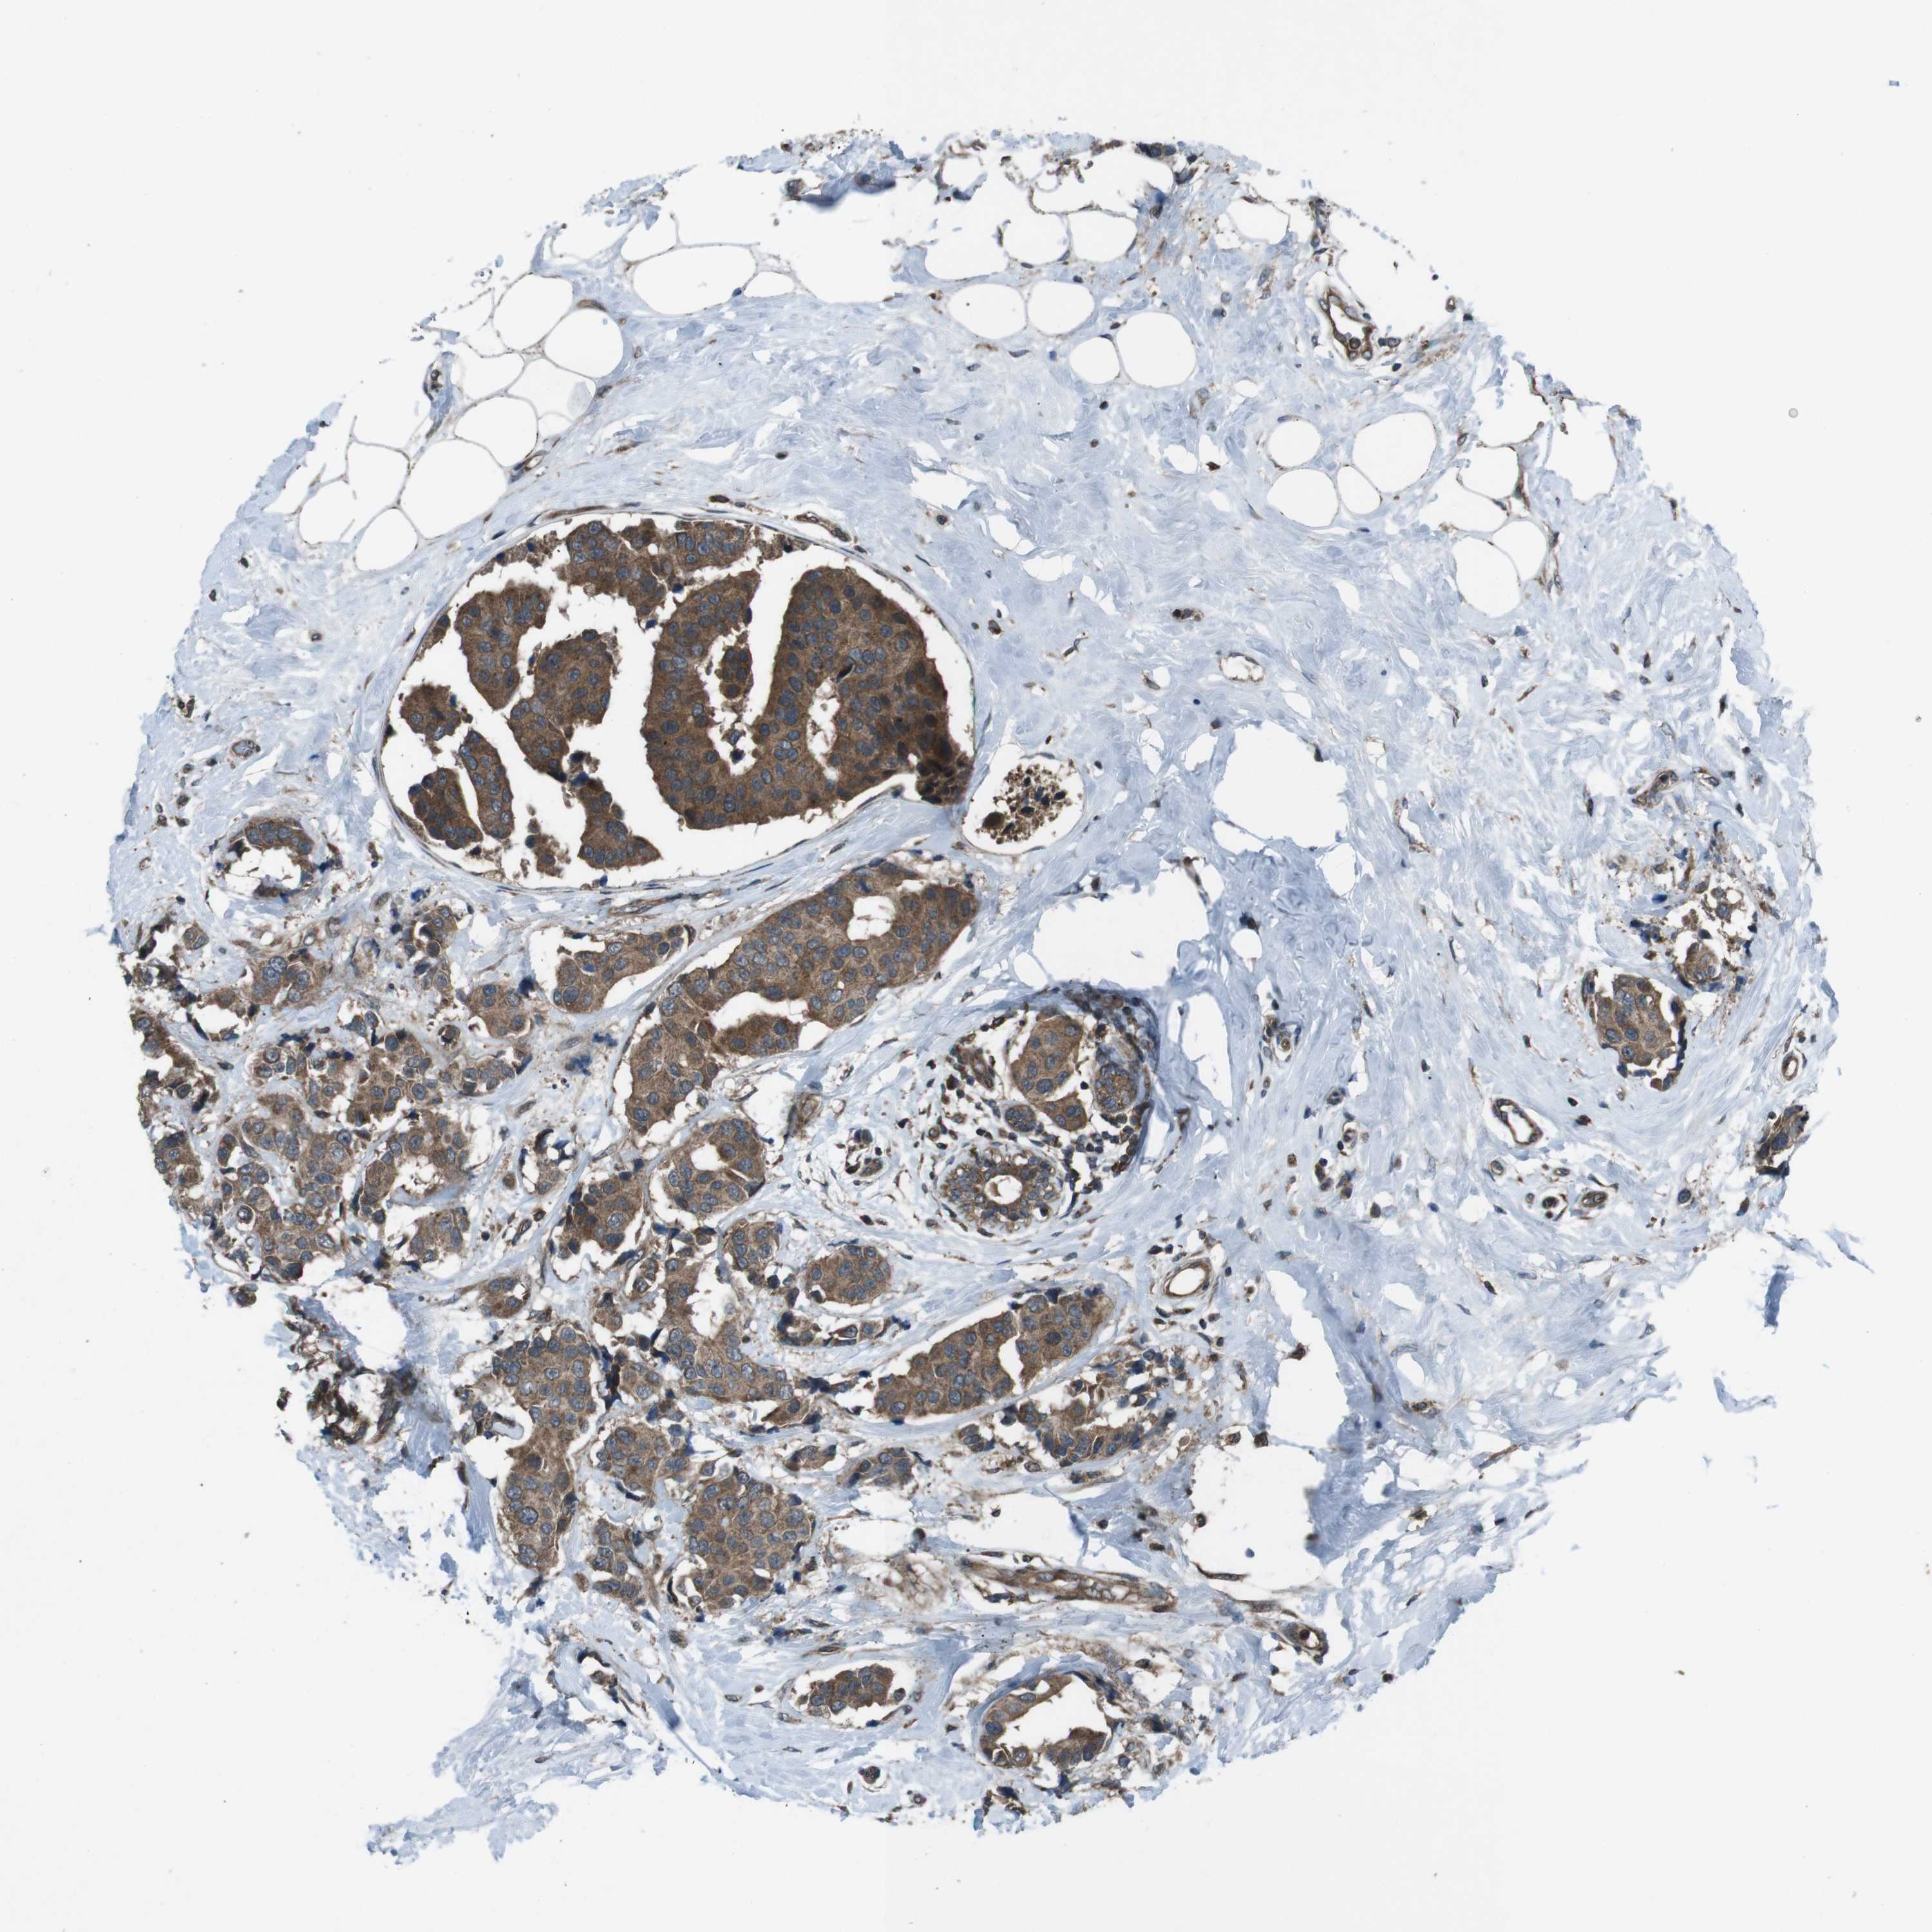

CANCER BREAST CANCER Show tissue menu

BRCA TCGA BRCA VALIDATION PROTEIN EXPRESSION

Breast cancer

Human cancer